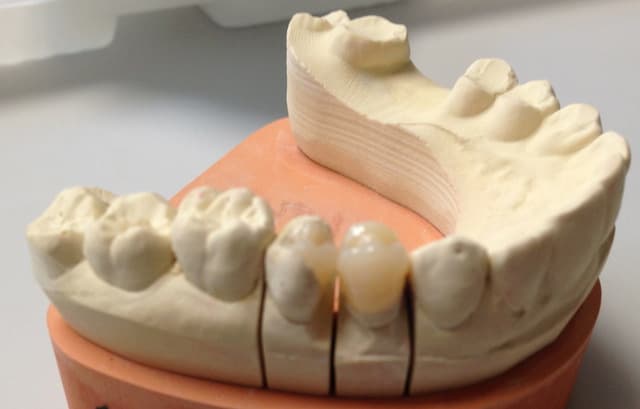

Alors comment traiteriez vous cette 24 asymptotique, qui présente un enorme délabrement sous gingival , notez que l'émail n'est plus soutenu par la dentine à aucun endroit ?

TE + inlay-core + couronne si on veut une reconstitution pérenne ...impossible de coller un inlay au sec...

Coiffage direct à la Biodentine (ou MTA), remontée de marge au compo et onlay emax. Pas d'endo si pas de symptomes.

1ère séance remontées de la marche distale au compo flow + compo de restauration / réalisation d'un IDS , le tout sous digue bien sur (voir radio jointe , désolé à l'envers))

Voici les photos toutes fraiches de ce matin.

Vos critiques sont bien sur les bienvenues je dois encore beaucoup m'améliorer sur les prises de teintes, et je m'y attelle en ce moment,, par contre en ce qui concerne la pérennité de la restauration…..ma patiente a sa dent bien vivante, aucun joint sous gingival , possibilité de réaliser une endo dans le futur sans détruire la restauration existante si besoin, possibilité re refaire un onlay dans quelques années si ça casse, toujours sur dent vivante…. bref la liste des avantages est très longue par rapport au classique endo-IC-CCM.